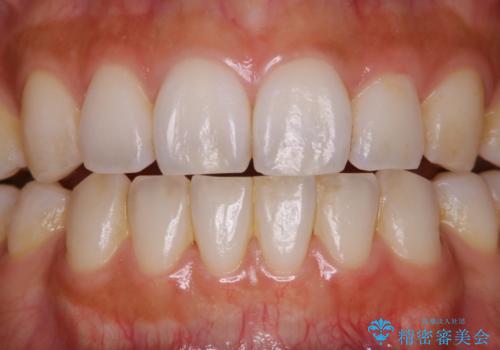

PMTCでスムーズにデンタルフロスが通るように

- フロスが以前よりも通りずらくなり、クリーニングしてほしいとのことでした。歯科医院でのクリーニングは3年ぶりとのことです。PMTC60分コースを行いました。

歯科医院で行なわれる専門家による徹底した歯面清掃をPMTC(Professional Mechanical Tooth Cleaning)といいます。専用の機器とフッ化物入り研磨剤を使用して、歯みがきで落とせない歯石や磨き残したプラークを中心に総ての歯面の清掃と研磨を行ない、齲蝕や歯周病になりにくい環境を整えます。

歯石が溜まると、歯と歯の間が埋め尽くされてしまい、デンタルフロスが通りずらくなったり、通せなくなります。